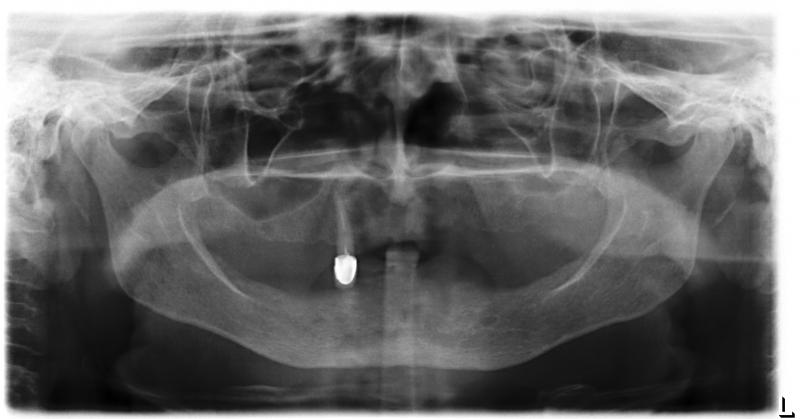

Установка 10 имплантантов на беззубую челюсть с помощью компьютерной программы: Первый визит пациентки

Первый визит пациентки